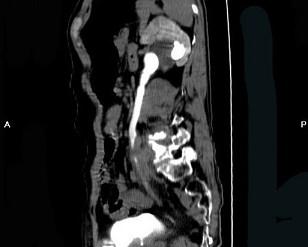

问题 男,59岁,反复尿频尿急尿痛4年余,尿常规检查:红细胞(+),白细胞(++),CT扫描如图示,下列说法正确的是 ( )

选项 A.左侧输尿管中下段输尿管管壁增厚,管腔狭窄 B.左侧侧输尿管上段扩张 C.考虑为输尿管结核 D.考虑为慢性输尿管炎 E.考虑为输尿管移行细胞癌

答案 ABD